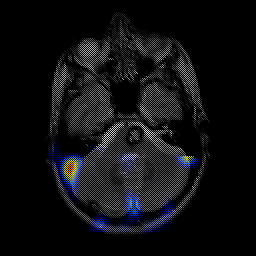

overlay -- Slice #6

[Home][Help][Clinical] Slice 6

Click on sagittal image to select slice. Click on thin tickmark to change timepoint, or thick tickmark for overlay.

Keith A. Johnson (keith@bwh.harvard.edu), J. Alex Becker (jabecker@mit.edu)